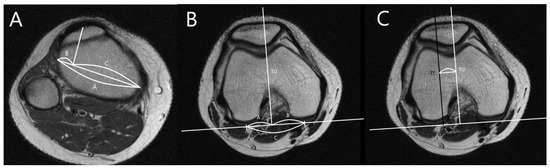

2.2. Radiographic Measurement